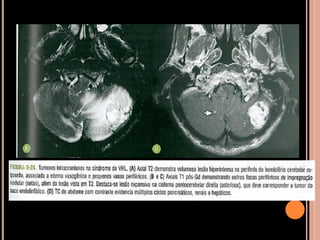

DOENÇA DE VON-HIPPEL LINDAU

 Hemangioblastomatose

 Tumores benignos e malignos múltiplos;

 Hemangioblastomas de retina, cerebelo e medula

espinhal;

 Rins: carcinoma de células renais;

 Adrenais: feocromocitoma;

 Pâncreas: tumores de células de ilhota e

adenomas serosos;

 Testículos: cistoadenomas epididimários;

 Cistos renais e pancreáticos múltiplos;

 1/3 dos hemangioblastomas cerebelares

relacionados à síndrome de VHL;

 2/3 dos hemangioblastomas medulares

 Associados à síndrome  idade mais precoce e

pior prognóstico;